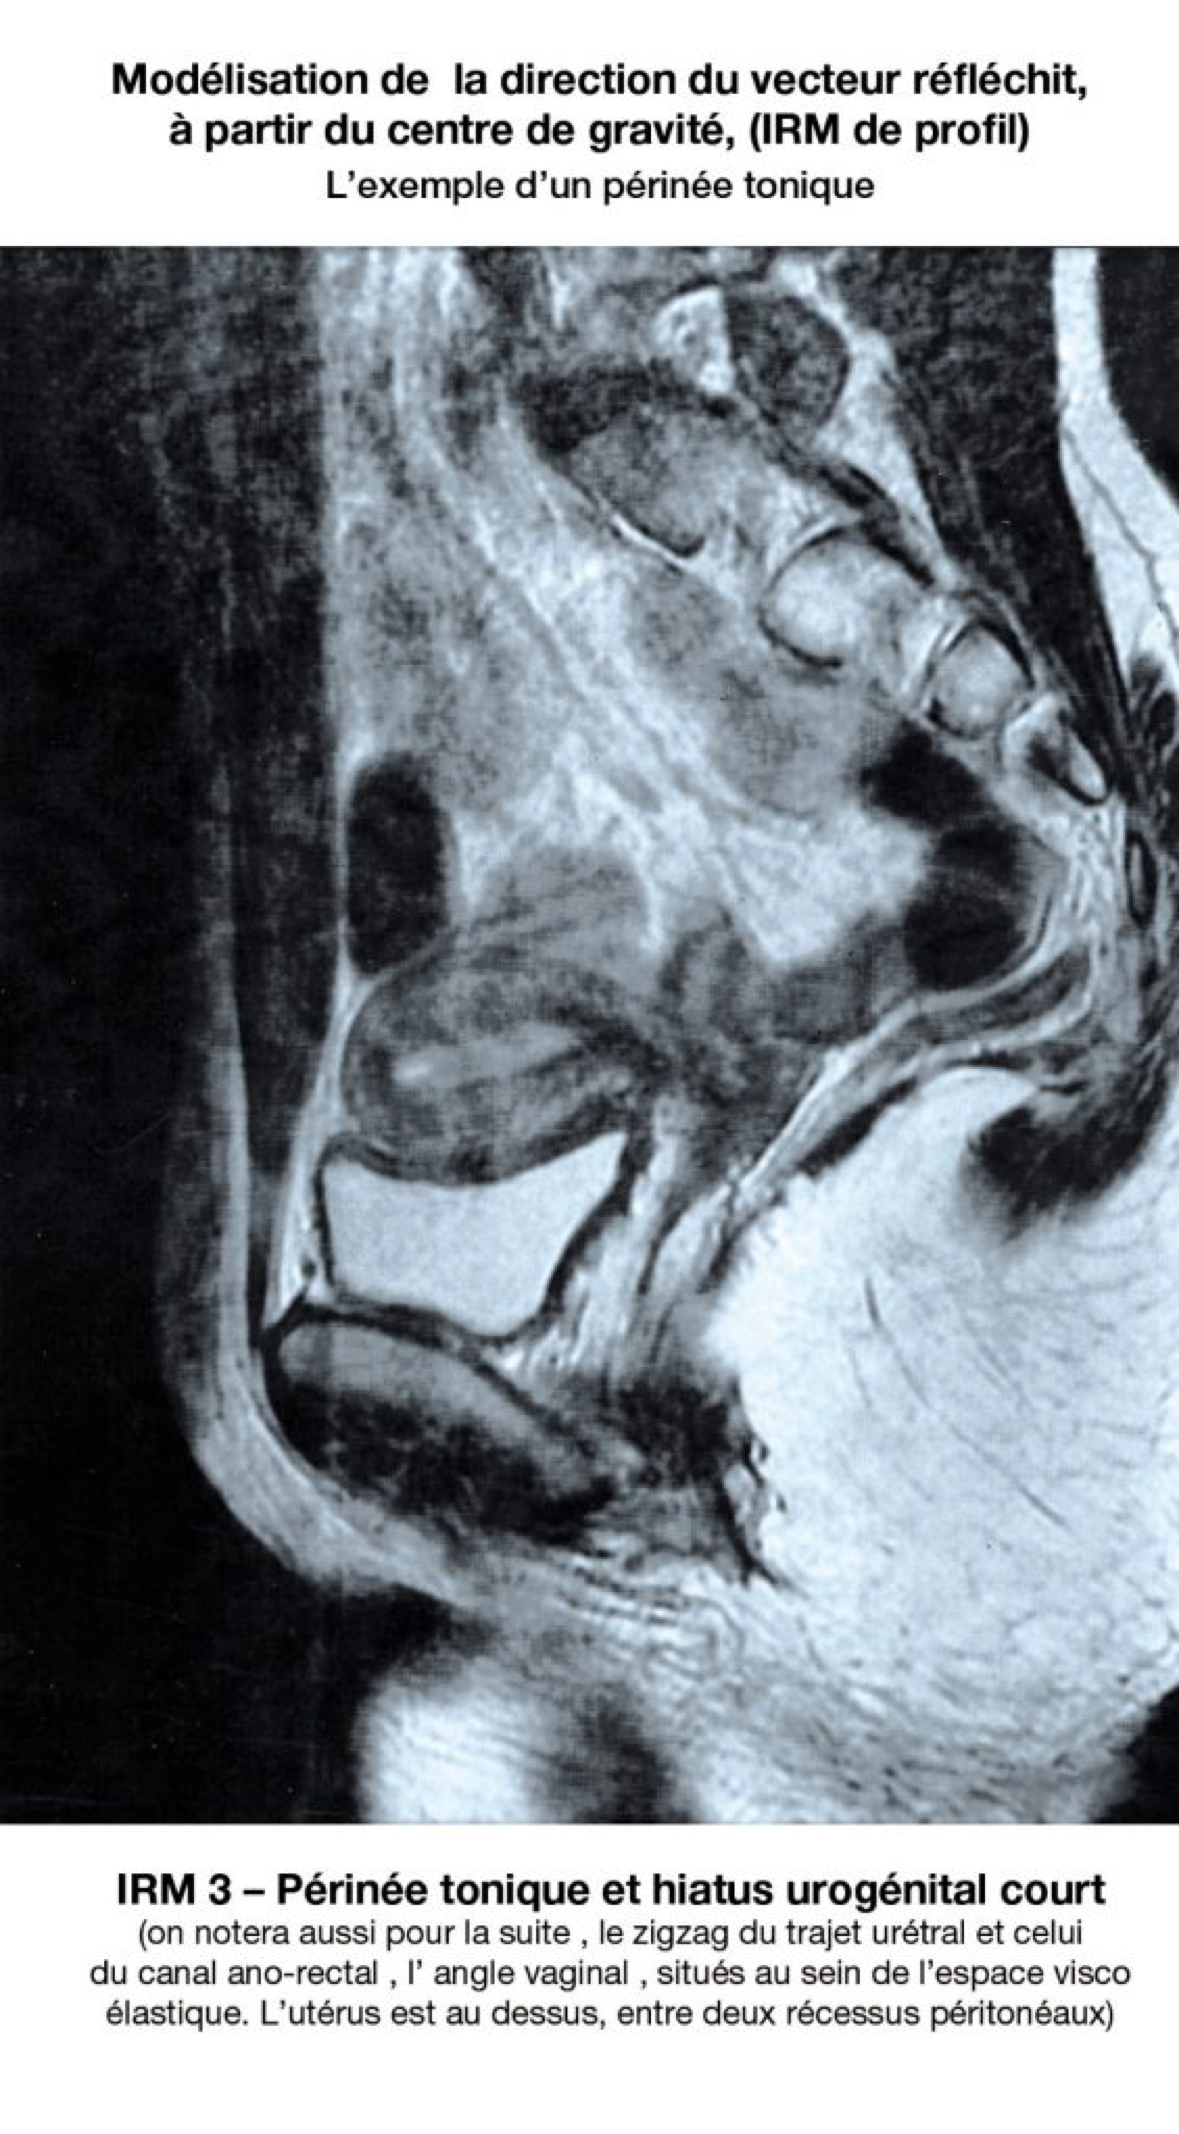

En postulat vectoriel, leur rôle essentiel pourrait être (???) celui de propriocepteurs ; et ils accentueraient et participeraient aux effets de clôture lors des glissements du tissu visco élastique pelvien. Divers arguments plaident en faveur de ces hypothèses : Pour l’urètre : 25% des vessies sont continentes à sphincter ouvert (ref 5). L’urètre continent de l’IRM n’est pas rectiligne. Il décrit un trajet en zigzag et la distance uretro pubienne faible. (Sa plicature peut être un mécanisme de continence). L’urètre continent n’est rectiligne que lors de l’incontinence physiologique, la miction (uretrographie mictionnelle).

Les formes de surface de la coupole, et la direction des vecteurs réfléchis varie en fonction du rétrécissement ou de l'élargissement de cette parabole, plus exactement, de ce paraboloïde pelvien. Ses formes varient en fonction de l’évolution physiologique. L’IRM pourrait modéliser les orientations vectorielles de chaque femme

Pour que le principe puisse trouver une application clinique, il faut pouvoir dessiner, ou modéliser les vecteurs de pression. La première étape est de déterminer la position du centre de gravité de cette pseudo parabole.

- L'IRM devrait étayer le choix des indications chirurgicales : un logiciel devrait permettre la modélisation du centre de gravité périnéal. Puis en reconstruisant la direction du plan de la parabole, la direction du vecteur des pressions abdominales telles qu’elles sont réfléchies par rapport à la position du hiatus urogénital.

La première étape serait la modélisation matricielle du centre de gravité sur une coupe coronale, c’est à dire proche du plan de réflexion du paraboloïde. La deuxième étape serait la construction du plan de réflexion du paraboloïde pelvien. Le programme établit la direction du vecteur réfléchit, selon les lois physiques de la parabole : le point d'application de la pression abdominale passe par le centre de gravité qui a été reconnu. - Le repositionnement chirurgical sera t il possible sans déséquilibrer le pelvis ?